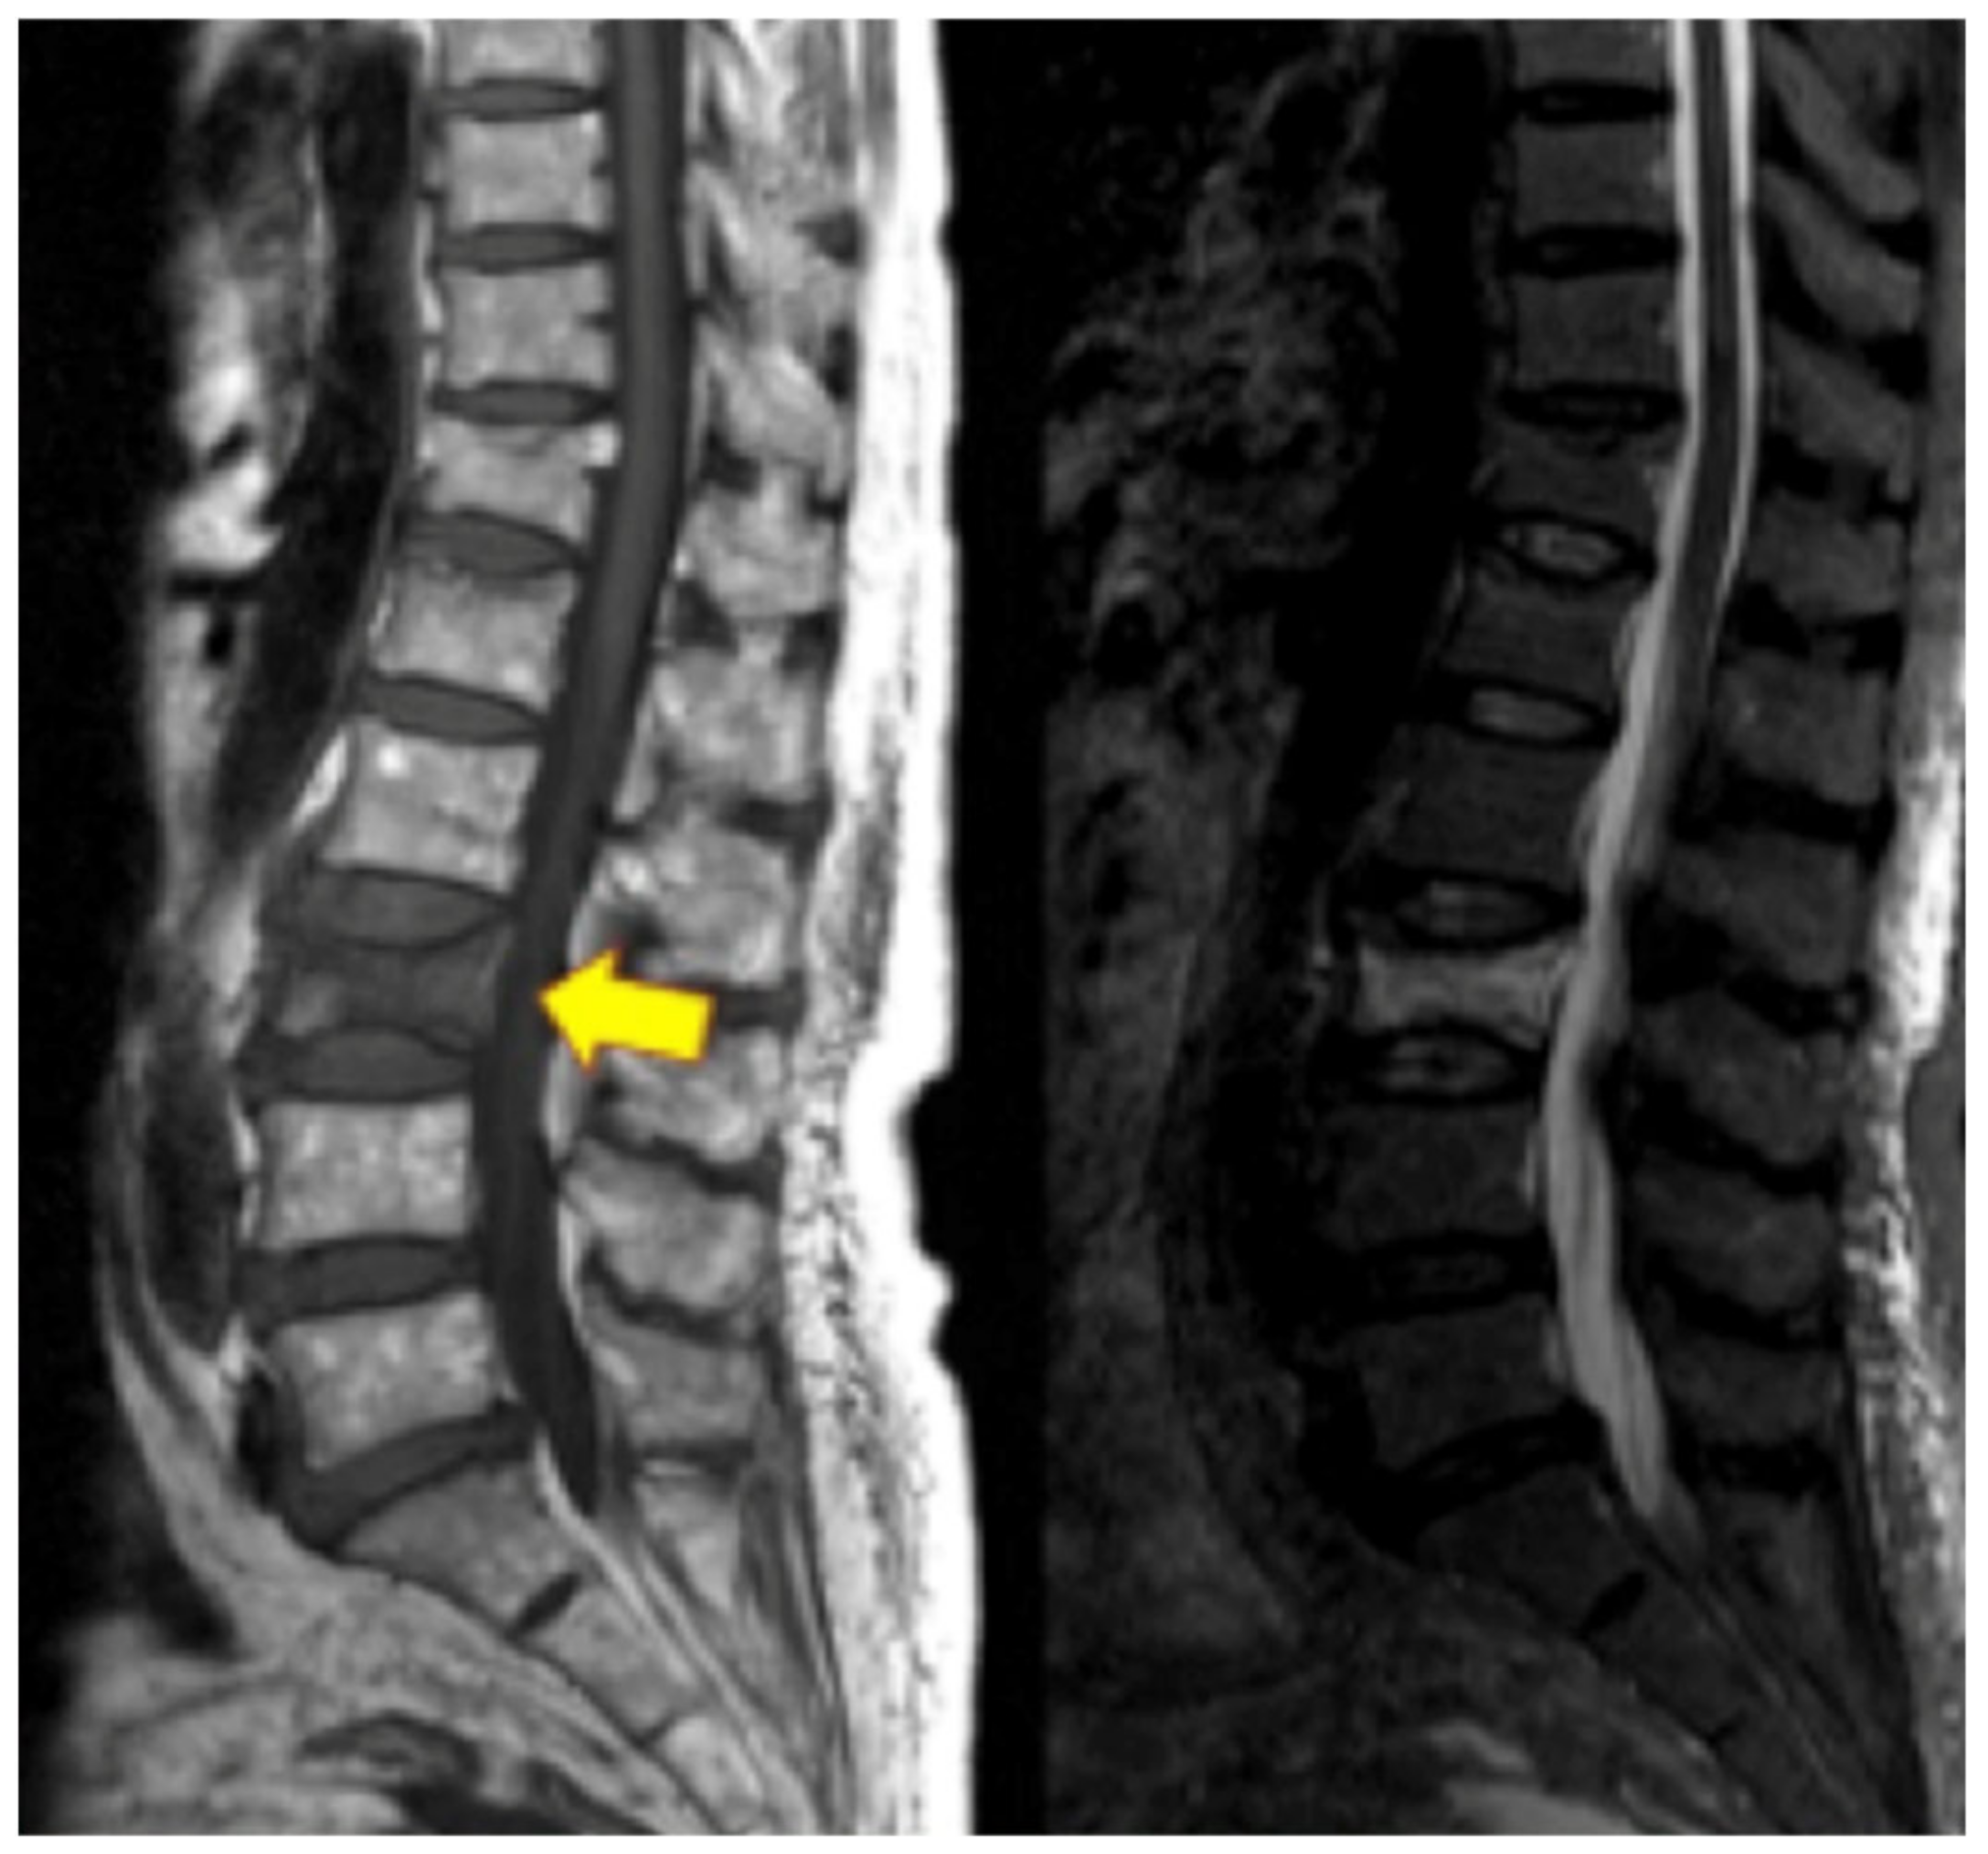

4.5. Vertebrogenic Pain

4.6. Basivertebral Nerve Ablation

- Modic, M.T.; Steinberg, P.M.; Ross, J.S.; Masaryk, T.J.; Carter, J.R. Degenerative disk disease: Assessment of changes in vertebral body marrow with MR imaging. Radiology 1988, 166, 193–199. [Google Scholar] [CrossRef]

- Jensen, T.S.; Karppinen, J.; Sorensen, J.S.; Niinimäki, J.; Leboeuf-Yde, C. Vertebral endplate signal changes (Modic change): A systematic literature review of prevalence and association with non-specific low back pain. Eur. Spine J. 2008, 17, 1407–1422. [Google Scholar] [CrossRef] [PubMed] [Green Version]

- Conger, A.; Schuster, N.M.; Cheng, D.S.; Sperry, B.P.; Joshi, A.B.; Haring, R.S.; Duszynski, B.; McCormick, Z.L. The effectiveness of intraosseous basivertebral nerve radiofrequency neurotomy for the treatment of chronic low back pain in patients with modic changes: A systematic review. Pain Med. 2021, 22, 1039–1054. [Google Scholar] [CrossRef] [PubMed]